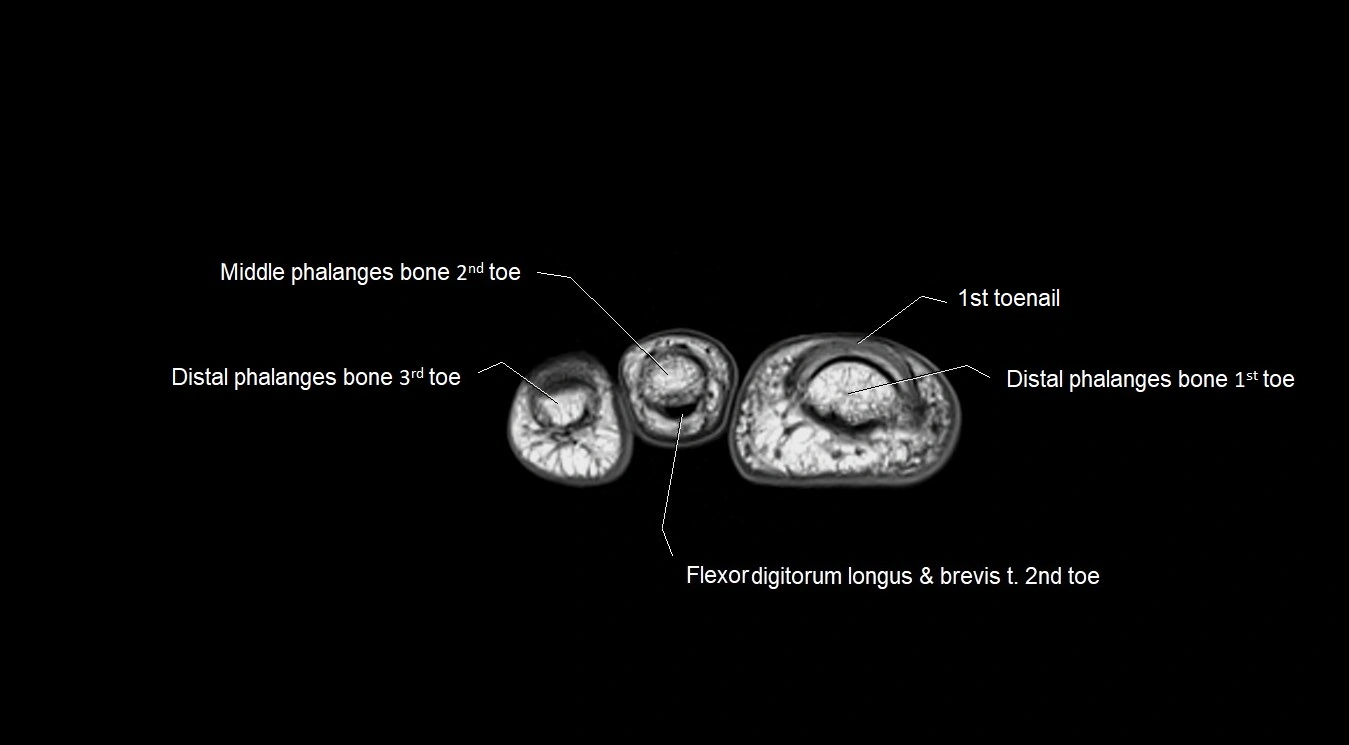

MRI image